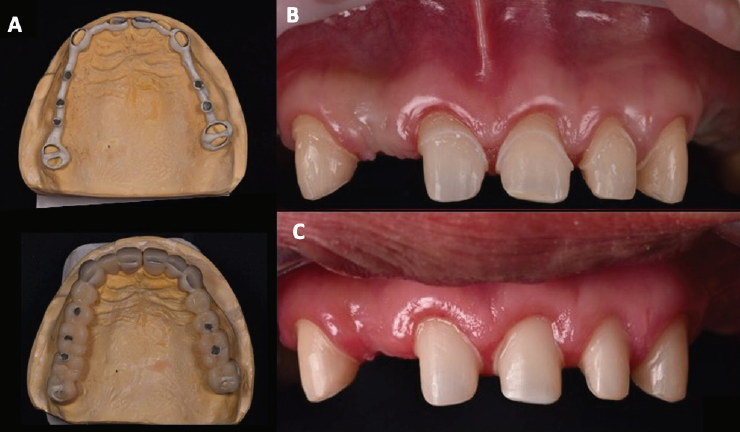

En la Fase I se realizaron extracciones de los dientes 26 y 47, ya que presentaban un pronóstico periodontal sin esperanza. Se optó por mantener temporalmente los terceros molares superiores con el fin de utilizarlos como pilares para los provisionales. Los dientes 31 y 32 presentaban un pronóstico periodontal regular y pobre respectivamente, por lo que se decidió realizar una regeneración ósea en la zona interdental. Se colocaron implantes en los dientes 36, 46, se realizó la elevación de ambos senos maxilares y se colocaron implantes en los dientes14 y 16. En la Fase II, se prepararon los dientes de la arcada superior 13, 11, 21, 22, 23, se optó también por preparar y mantener temporalmente los terceros molares 18 y 28 para soportar un provisional de acrílico (AlikeTM, GC® America Inc) seccionado en hemiarcada de central a tercer molar, con refuerzo de estructura metálica (Figura 3. A). Se realizó de esta manera debido a los largos periodos de cicatrización que se presentarían durante el tratamiento, para evitar fracturas por la longitud de las brechas desdentadas y para mantener dimensión vertical. Se realizaron alargamientos de corona en los dientes 13, 11, 21, 22, 23 (Figura 3. B). Un mes después se re-prepararon los dientes para colocar el margen a nivel equigingival. Se tomó una impresión con alginato (Hydrogum 5, Zhermack® Dental) para realizar un nuevo encerado y un nuevo provisional de acrílico utilizando la misma estructura metálica del provisional anterior (Figura 3. C). En la arcada inferior se realizaron preparaciones horizontales para carillas en los dientes 31, 32, 33, 41, 42 y 43 con el fin de restituir el tejido dental perdido y lograr un contacto con los dientes superiores. Se colocó un provisional de resina bisacrílica (Protemp™, 3M™).

Para la cementación, se llevó a cabo mediante técnica de aislamiento absoluto. Las restauraciones libres de metal fueron acondicionadas con ácido fluorhídrico (Porcelain Etch 9%, Ultradent™) durante 20 s, se lavó, se colocó ácido fosfórico al 37% (K-Etchant Syringe, Kuraray Noritake Dental Inc) con 20 s de fricción para eliminar residuos, seguido por lavado de 20 s, se secaron y se aplicó primer cerámico (Clearfil™ Ceramic Primer Plus, Kuraray Noritake Dental Inc) el cual se dejó secar por 60 s. En cuanto al acondicionamiento dental, se arenó la superficie con óxido de aluminio de 30µm, se lavó, se grabó el esmalte con ácido fosfórico al 37% (K-Etchant Syringe, Kuraray Noritake Dental Inc) durante 15 s, se lavó y se colocó Tooth Primer (Panavia™ V5 Clear, Kuraray Noritake Dental Inc). Las coronas (21, 22 y 23), la prótesis fija (11 y 13) y carillas (31, 32, 33, 41, 42 y 43) de LS2 se cementaron con cemento dual (Panavia™ V5 Clear, Kuraray Noritake Dental Inc). Las prótesis fijas sobre implantes (14, 16, 24 y 26) fueron cementadas con cemento dual (Panavia™ V5 opaque, Kuraray Noritake Dental Inc) utilizando hilo para evitar restos de cemento subgingival. Las coronas sobre implantes (36 y 46) se atornillaron a 35Nc. En la Figura 4. A se observan las restauraciones finales en boca de la arcada superior y en la Figura 4. B, las de la arcada inferior. Finalmente se verificó la oclusión con papel de articular, se eliminaron los contactos prematuros y se entregó una férula oclusal con guías anteriores. En la Figura 4. C se observan las fotografías de la paciente con los resultados finales del tratamiento. En la Fase IV se citó para valoración y posteriormente requerirá revisiones periódicas para realizar el mantenimiento de las prótesis.

Figura 4 Fotografías finales. A. Fotografías extraorales de frente y sonrisa. B. Fotografías intraorales, superior e inferior.

Como resultado se logró una rehabilitación oral completa de la paciente en clase II de Angle mediante los procedimientos quirúrgicos pre protésicos (regeneración ósea, elevaciones de seno, colocación de implantes y alargamientos de corona) que permitieron acondicionar la cavidad oral para recibir las restauraciones finales (prótesis fija, coronas, carillas, prótesis fijas sobre implantes y coronas individuales sobre implantes) manteniendo la dimensión vertical y con una adecuada adaptación a los tejidos gingivales. Se logró disminuir la sobremordida horizontal corrigiendo la angulación axial de los dientes anteriores por medio de restauraciones (prótesis fija, coronas y carillas), además, se logró un contacto oclusal entre los dientes anterosuperiores y anteroinferiores. También se cerraron los triángulos negros (espacios interdentales) en el sextante anteroinferior al colocar las carillas. Se estableció una oclusión estable de arco acortado en relación céntrica al colocar las prótesis sobre implantes. Por lo anterior se puede decir que se lograron los objetivos funcionales, estéticos y biológicos de acuerdo con las expectativas de la paciente.